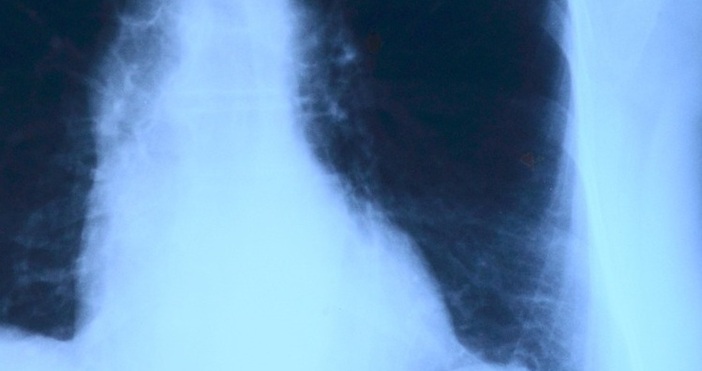

Рентгенова снимка разкрила голям метален нож, заседнал в гръдната кухина – областта, където се намират сърцето и белите дробове. Острието, което преминавало от задната страна на гръдния кош към предната, било проникнало през гърба близо до дясната лопатка, като се вмъкнало между петото и шестото ребро и стигнало с върха си до пространството между третото и четвъртото ребро отпред. Компютърна томография показала и зараснали счупвания на лопатката и няколко ребра. Около острието имало натрупани слоеве гной и мъртва тъкан.